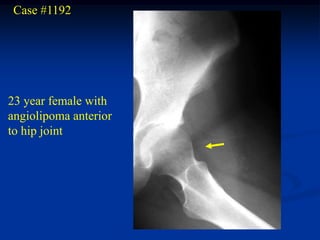

Case #1192

23 year female with

angiolipoma anterior

to hip joint

Axial T-1 MRI

Sagittal T-1 MRI

Coronal T-1 MRI

Case #1192 23 yearfemale with angiolipoma anterior to hip joint